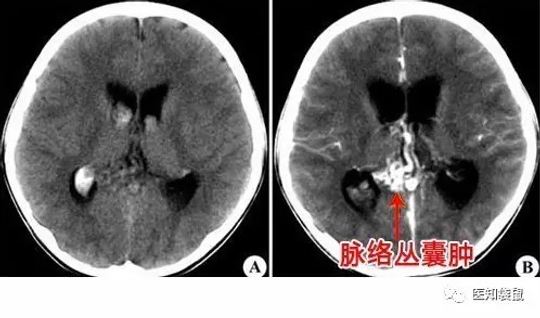

2、脉络丛囊肿

脉络丛囊肿是指侧脑室脉络丛散在的、直径≥3mm的小囊肿,可发生在单侧或双侧,也可单发或多发。

脉络丛囊肿的出现与染色体异常有一定关系,所以,当发现胎宝宝有脉络丛囊肿后,需要仔细检查胎儿有无其他结构的异常,尤其是双手,以辅助除外胎儿染色体畸形的可能。

如果胎儿只有脉络丛囊肿,没有发现其他结构异常,则无需过于担心,通常只需要在孕26周后复查B超。因为90%以上胎宝宝的脉络丛囊肿会在妊娠26周以后消失,也不会对孩子的智力造成影响。

但如果胎宝宝囊肿呈进行性增大,或者还合并有其他的结构异常,比如说肾盂积水、肾脏积水、胎宝宝紧握拳头等,则提示胎宝宝患18-三体综合症的可能性很大,需要进行羊膜腔穿刺检查,分析胎宝宝染色体核型,以判断胎儿是否有染色体畸形。